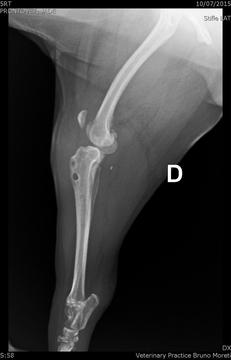

durante o tratamento desloquei meu joelhinho e precisei operar a outra patinha.

Mesmo com minha vovó me carregando no colo até para fazer xixi, a cirurgia não

deu certo (não sabemos pq) e tive que fazer um “retoque” , que não adiantou em nada, e mamãe até acha que eu piorei. Desde a primeira cirurgia do joelho eu fico deitada o tempo todo na minha caminha, e minha vovó me da até água na boquinha!O problema é que a mamãe teve que pagar o que ela estava devendo na clínica antiga, e a conta ficou em quase R$ 7.500,00. Isso mesmo gente... Esse valor todinho =/Mamãe e vovó resolveram me levar em novos veterinários que estão cuidando de mim! Agora tenho mais três tios que querem ficar mexendo nas minhas dobrinhas lindas! Fiz sessões de acupuntura, que me ajudaram muito e sinto que agora vai dar tudo certo!

Minha mamãe queria pedir a ajuda de vocês com algumas doações, pois vocês

lindos e preciosos!Em Novembro passei por uma nova cirurgia na perninha, dessa vez com um especialista em ortopedia. Isso gerou novos gastos para a mamãe, mas ela está tão feliz em ver que agora estou me recuperando!!Essa é minha página, acompanhem!